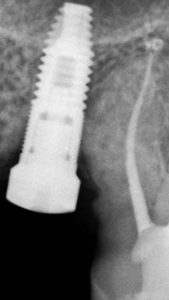

El sistema radiográfico digital New IDA cuenta con un sensor que usa las tecnologías asociadas del CMOS (Complementary Metal-Oxide-Semiconductor), fibra óptica protectora y centelleada. Ese sensor fue fabricado para adquirir la imagen de rayos x digital de alta calidad de la arcada humana y sus estructuras.El proceso de adquisición es realizada posicionado el sensor en la parte interna de la boca atrás de la estructura que se desea realizar el examen.

La estructura debe ser expuesta a una dosis de rayos x usando una fuente externa. Una vez expuesto, el sensor realiza una conversión de los fotones de rayos x en una señal digital y enseguida transfiere para una computadora vía conexión USB (Universal Serial Bus). El software de gestión de imagen dental realiza el interfaz con el sistema New IDA y el usuario, podrá visualizar, mejorar, almacenar, enviar, imprimir entre otras funciones

Es el sensor digital intraoral de DabiAtlante que ofrece imágenes de solución eficiente para obtener un diagnóstico más claro, preciso y avanzado.

Captura imágenes de alta definición en tiempo real.